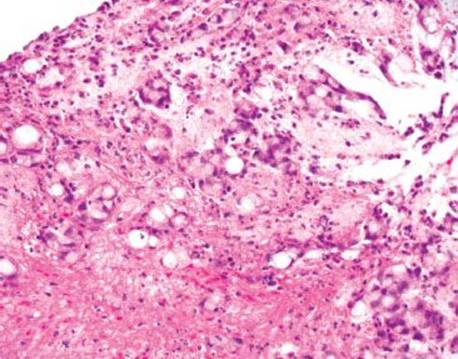

Figure 4.273 Endometriosis. Higher power of previous image. Cilia are not definitively identified in this suboptimal specimen. Biopsies of the lesion had raised concerns for an infiltrating adenocarcinoma because the glandular elements were not recognized as endometrial, the overlying reactive changes were interpreted as dysplasia, and numerous mitotic figures were seen.

Endometriosis is the presence of at least two of the three following features outside of the uterus: endometrial glands, stroma, and hemorrhage (Figs. 4.271–4.273). Up to 37% of women with endometriosis have intestinal involvement, and any layer of the bowel can be involved. The clinicopathologic presentation is diverse and presentations can overlap with appendicitis, IBD, diverticular disease, infectious colitis, a surgical acute abdomen, malignancy.125–128 Endometriosis involving the rectum commonly presents as bloody diarrhea. Associated pathologic findings can include strictures, ulceration, fissures, ischemia, and intussusception.125 The lesions can appear as polyps or bleeding mass lesions, raising clinical concerns for malignancy. The overlying colonic epithelium can be markedly reactive and mimic dysplasia, leading to the misdiagnosis of colonic adenocarcinoma. Occasionally, only the stromal component is seen and a diagnosis of sarcoma is entertained. In these cases, usually the endometrial glands can be identified on deeper sections. Confirmatory immunohistochemical stains include ER and PR to highlight the glandular components and CD10 to highlight the endometrial stroma.